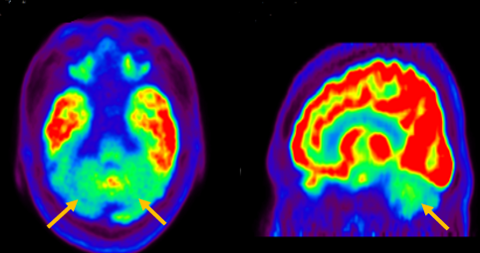

진행 핵상 마비는 대표적인 파킨슨 증후군 중의 하나입니다. 파킨슨병과 다른 점은 질병의 초기부터 중심을 잡기 어려운 체위 불안정이 나타나 자주 넘어진다는 것입니다. 파킨슨병의 경우 질병이 상당히 진행된 뒤에 체위 불안정이 나타납니다. 또한 진행 핵상 마비에서는 목 주위 근육을 비롯한 몸 중심 근육의 경축이 나타나, 목을 뒤로 젖히면서 걷는 모습이 보입니다. 그리고 눈의 운동을 조절하는 기능에 장애가 나타나 아래쪽을 바라보는 데 문제가 생겨 계단을 내려갈 때 어려움을 겪는 경우가 많습니다. 진행 핵상 마비가 의심되는 경우, 뇌 자기공명영상(MRI)에서 중뇌의 위축이 비정상적으로 심하게 나타나는 소견을 확인하거나, 뇌포도당 양전자 단층촬영(PET)에서 전두엽과 중뇌의 대사 기능이 저하된 소견을 확인하여 진단에 참고할 수 있습니다.

[진행핵상마비 환자의 뇌포도당 양전자 단층 촬영에서 확인되는 중뇌의 대사 저하 소견]